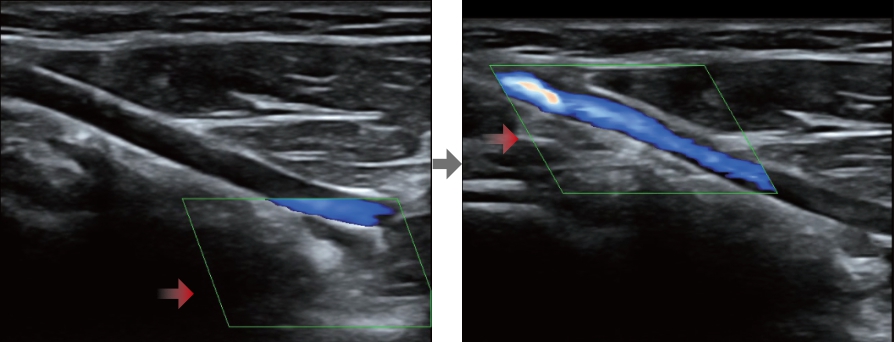

Smart Track

Smart Track biedt snelle en intelligente optimalisatie voor vasculaire beeldvorming met slechts ├®├®n druk op de knop. Het optimaliseert het kleuren-, power- en PW-spectrum met zelftracking en reduceert het aantal tijdrovende stappen. De workflow voor vasculair onderzoek wordt daarmee vereenvoudigd met een optimale weergave.